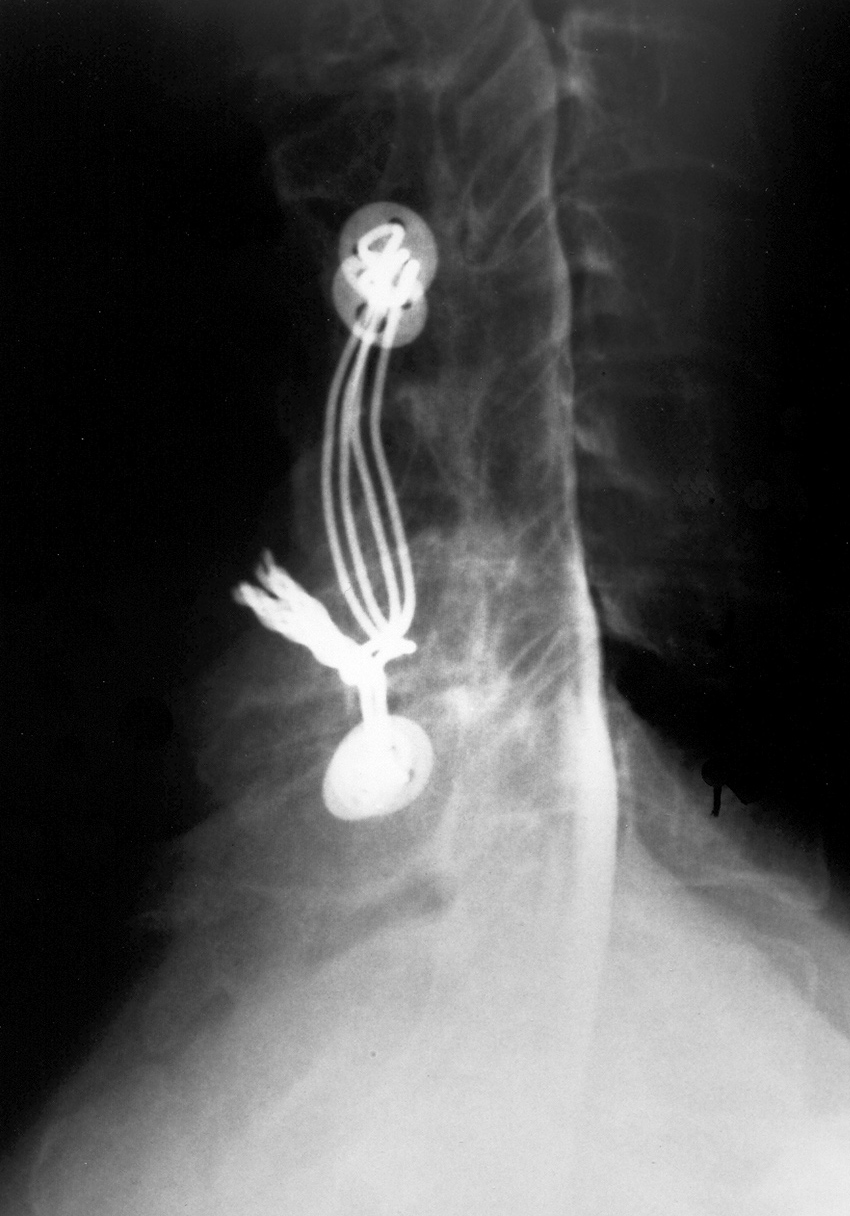

| Child with severe intracranial and cervical spine injuries with bilateral cranial stabilization tongs, an endotracheal tube, an oroogastric tube, and a feeding tube entering via the nose.

From Hunter, 2004 |

Cranial (head) tongs are used to stabilize the head and neck in a patient with a cervical spine fracture. One or more screws penetrate the outer table of the skull on each side. They are connected to each other by horizontal or vertical bars on each side that are attached to an external traction device.